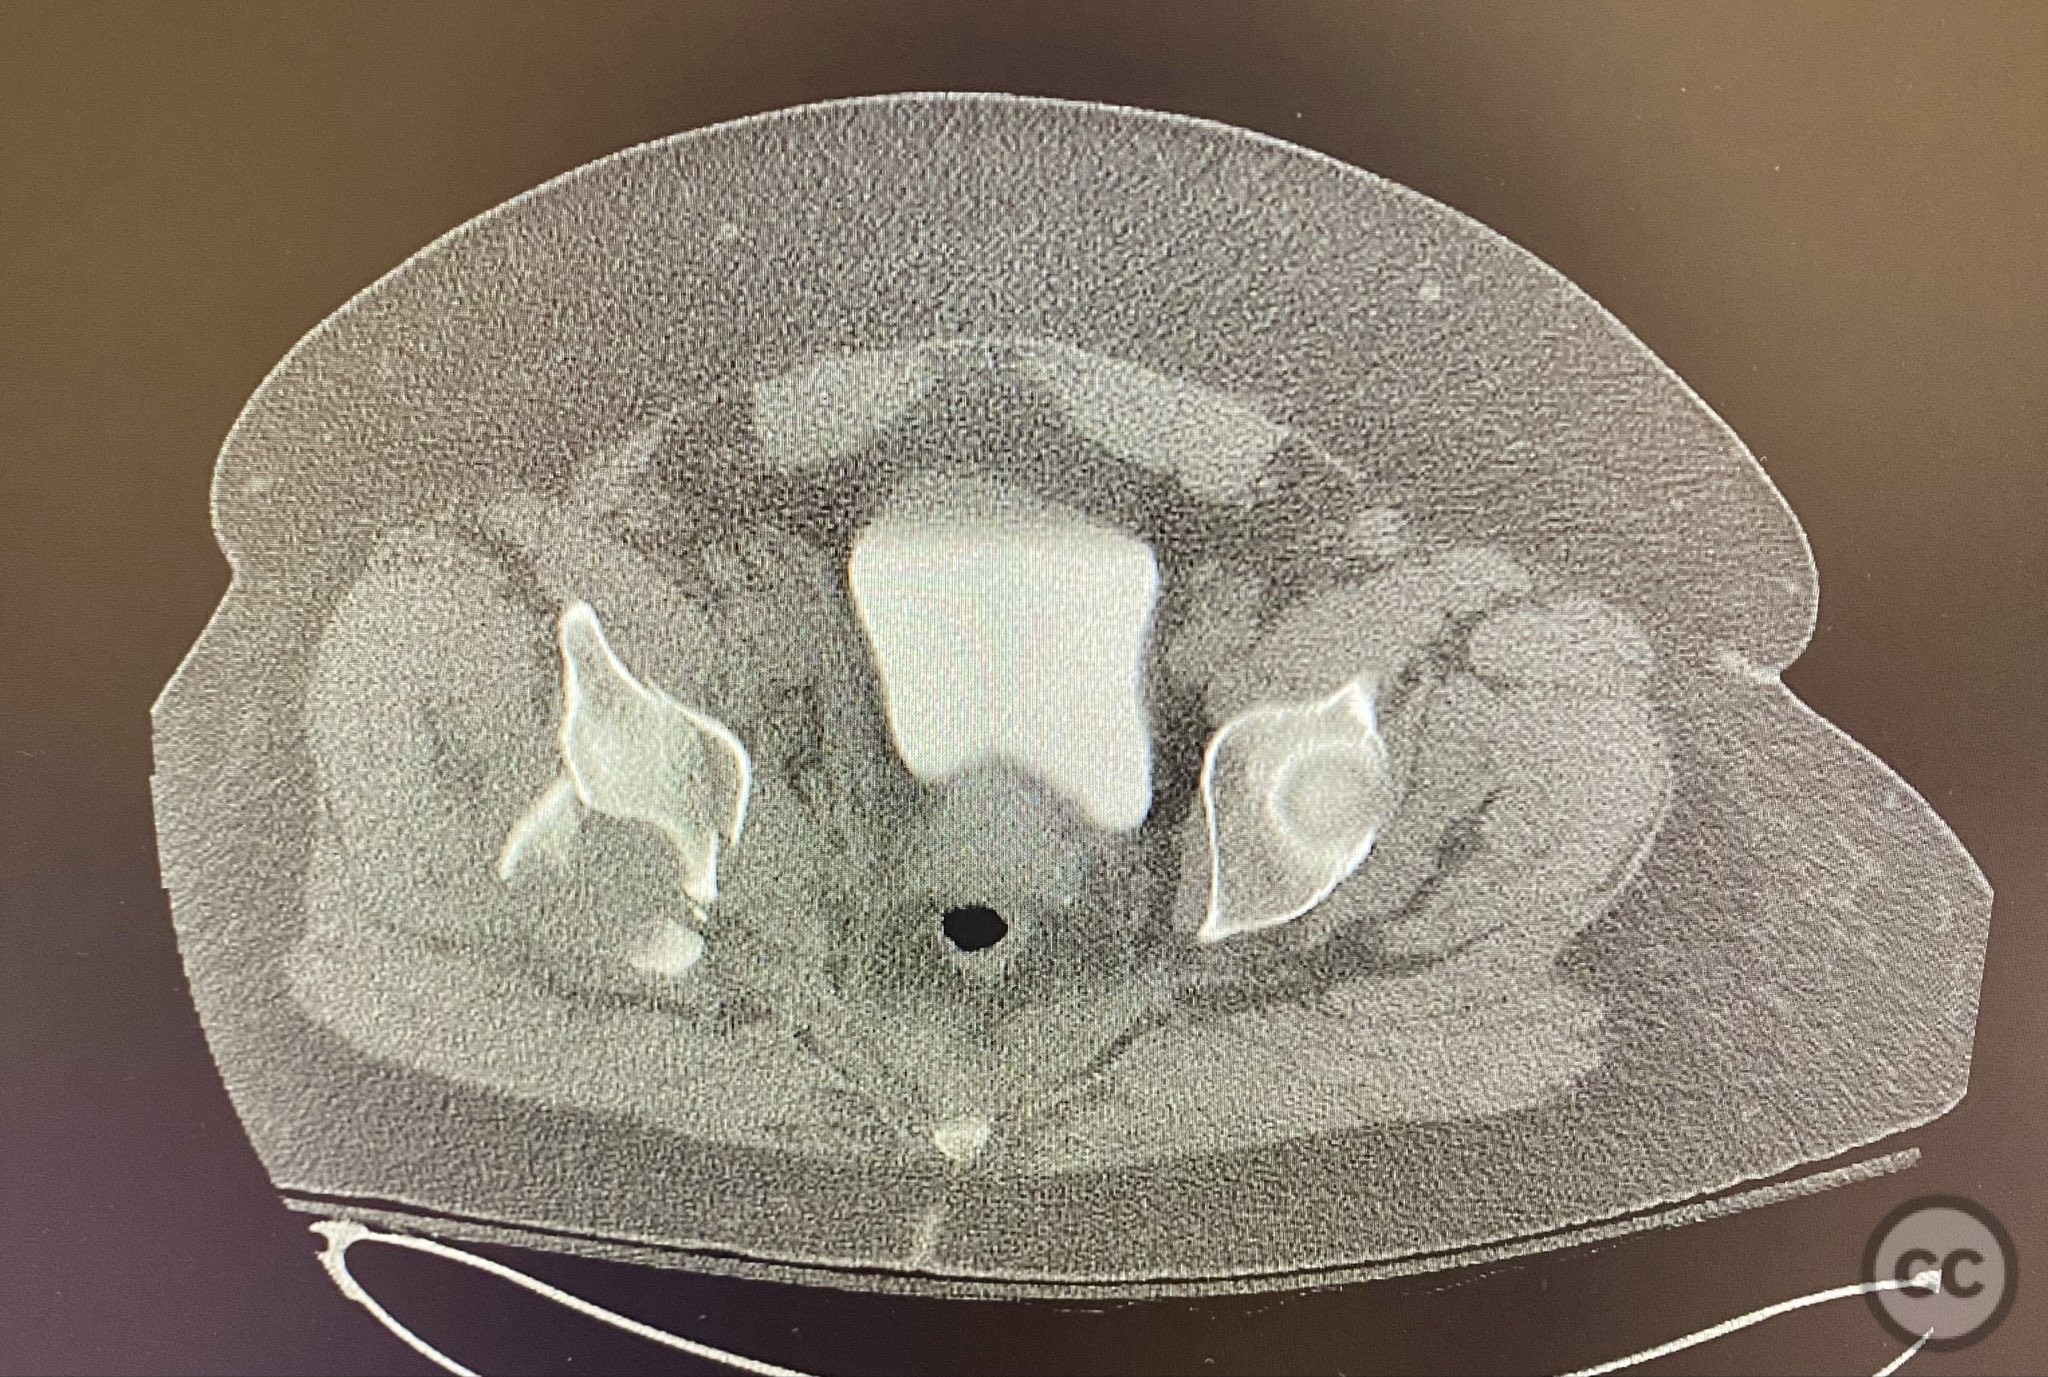

Clinical and radiological findings:  A high-speed motor vehicle collision resulted in a closed transverse acetabular fracture with associated comminuted posterior wall (PW) fracture-dislocation. The femoral head exhibited impaction and comminution, with local cancellous bone crushed and the femoral head itself also sustaining compressive injury from the denser acetabular bone. Neurovascular examination was unremarkable. Initial CT imaging delineated the acetabular fracture planes, displacement, comminution of the posterior wall, femoral head impaction, and absence of soft tissue attachment to the caudal PW fragment.